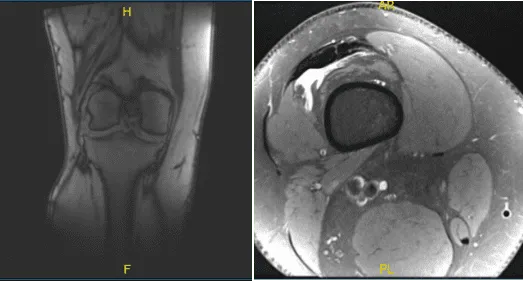

Se realizó una resonancia magnética y una radiografía, que muestran una rotura del menisco lateral. Hablamos sobre las opciones de tratamiento y el paciente optó por el manejo quirúrgico. Hablamos sobre los riesgos, beneficios y complicaciones de la cirugía. Hablamos sobre la posible reparación meniscal frente a la meniscectomía. El paciente lo entendió y firmó un consentimiento informado.